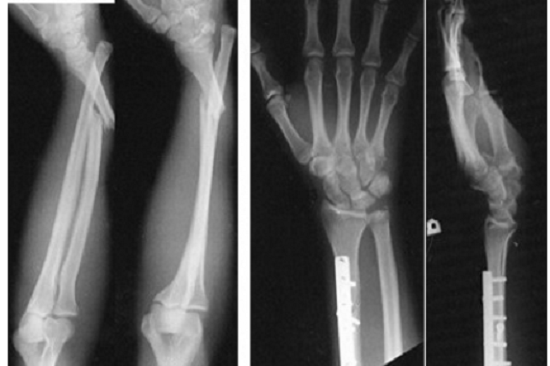

Tùy từng loại gãy xương, vị trí gãy, bác sĩ sẽ cho bệnh nhân đi chụp xquang để chẩn đoán sơ bộ. Nếu thấy cần thiết bác sỹ sẽ cho người bệnh đi chụp thêm phim CT hoặc Cộng hưởng từ (MRI) để chẩn đoán chính xác hơn và đưa ra chỉ định phẫu thuật.